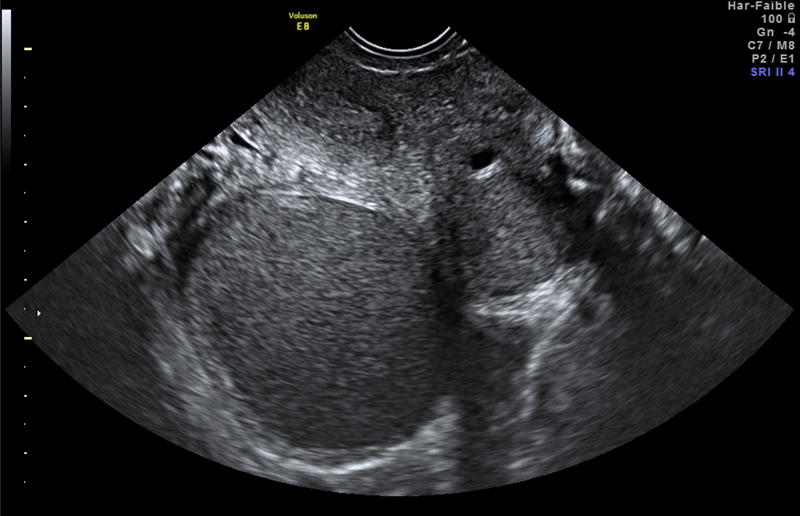

Problèmes soulevés par l'errance diagnostique La stratégie nationale de santé a souligné la problématique de l'errance diagnostique, errance diagnostique qui a été estimée à plusieurs années, en moyenne 7 ans, dans les pays de l'OCDE [4]. Cette estimation a été confirmée par des études réalisées en France. Le délai entre le début des symptômes et le diagnostic s'explique à la fois par la banalisation des symptômes, les femmes, souvent jeunes, souffrent sans que la demande de soins soit effective, la banalisation des symptômes peut être également le fait de l'entourage familial, scolaire ou bien professionnel. L'autre volet de ce délai concerne l'errance médicale, le diagnostic n'étant pas forcément évoqué, ni posé lors des premières consultations. Une étude comparant le parcours de soins des femmes Australiennes aux femmes Françaises [5] montre que la stratégie de recours à la coelioscopie diagnostique permettait de réduire les délais diagnostiques, au prix d'une chirurgie dont l'utilité thérapeutique, c'est-à-dire pour soigner la souffrance, me paraît discutable. En France le diagnostic repose principalement sur les méthodes d'imagerie, échographie endovaginale et/ou IRM [6]. Cette stratégie, basée sur l'imagerie, explique l'extrême variabilité des délais diagnostiques d'une patiente à l'autre, en fonction du protocole de prescriptions des examens diagnostiques ou de l'accès à l'imagerie de référence. La stratégie de coelioscopie diagnostique a, en effet, été largement remise en question en France depuis les années 2000 par le développement important de l'imagerie médicale de référence et la formation des échographistes et des radiologues. Les publications des centres de référence sur l'imagerie [7] montrent en effet que l'échographie trans-vaginale de référence, pratiquée par un médecin expérimenté dans l'endométriose, qu'il soit gynécologue ou bien radiologue, donne de bons résultats avec une sensibilité variant selon les lésions, mais avoisinant les 60 % en cas d'endométriose profonde et les 100 % en cas de kyste endométriosique (Figure 2). L'IRM, qui a une bonne réputation sur le diagnostic, obtient une sensibilité plus importante pour l'endométriose profonde (Figure 3), est accessible à la relecture, mais cet examen peut générer des faux positifs dans le cas d'atteintes mineures, ce qui pose un problème au niveau sociétal et limite le recours à l'IRM en première intention. La réalité du diagnostic par l'imagerie est plus sombre car de fait l'accès à l'échographie de référence, par des praticiens réellement expérimentés à l'imagerie de l'endométriose, est faible et le plus souvent seuls les kystes endométriosiques sont détectés par l'échographie de routine. L'IRM permet une relecture dès lors que la séquence d'imagerie est réalisée de façon satisfaisante, mais là encore si cet examen est pratiqué dans une population à faible prévalence de l'endométriose, par exemple les dysménorrhées primitives de la jeune fille, le taux d'examens faussement positifs sera inflationniste et risque de «labelliser» à tort des jeunes femmes comme porteuses de cette maladie avec tous les risques iatrogènes que cela comporte. À l'inverse, les conséquences du non diagnostic posent également plusieurs problèmes, dont voici les trois principaux : Le premier problème serait la possibilité d'une évolution de la maladie vers les formes les plus graves si elles ne sont pas prises en charge à temps. Cette possibilité d'évolution est attestée pour une partie des femmes qui présentent des formes sévères lors du diagnostic, mais pas pour toutes. Le deuxième problème est la conséquence de l'évolution au cours du temps de la symptomatologie douloureuse chronique, invalidante, intense, quotidienne, qui va peu à peu transformer le syndrome douloureux purement lié à la maladie endométriosique en un syndrome douloureux pelvien complexe avec des renforcements douloureux, appelé sensibilisation. Cette sensibilisation peut se manifester tant au niveau pelvien qu'au niveau médullaire, tronculaire ou cérébral. Ce passage vers l'état de syndrome douloureux pelvien complexe rend la prise en charge des femmes souffrant d'endométriose beaucoup plus difficile [8]. La troisième conséquence du non diagnostic est l'absence de reconnaissance des femmes qui souffrent. La reconnaissance médicale étant vécue comme une source d'apaisement et a un aspect largement bénéfique sur l'évolution douloureuse. Nommer la maladie, savoir pourquoi on souffre est une revendication légitime des femmes, des patientes [9].

Figure 2 Aspect caractéristique de kyste endométriosique à l'échographie transvaginale